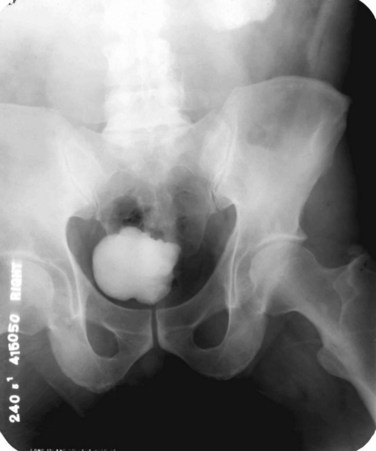

Tuberculosis of the ureter is commonly seen as a rigid, straightened “pipe-stem” ureter. A beaded, corkscrew appearance is sometimes also seen. Ureterovesical junction obstruction is caused by tuberculous cystitis or strictures of the distal third of the ureter (Fig. 16–4). Secondary stone formation on top of this stricture is an occasional finding. The cystogram films may show a small contracted bladder due to excessive fibrosis (Fig. 16–5). Of note, although IVU is being phased out by CT-urography in many developed countries (Stacul et al, 2008), IVU continues to be a reliable imaging modality for genitourinary TB in most parts of the world.

Augmentation cystoplasty and bladder substitution are options in the management of the tuberculous contracted bladder. A capacity of less than 100 mL is commonly the indication to augment. Extremely contracted bladders (thimble bladders of 20 mL capacity) are best managed by orthotopic bladder substitution (Hemal and Aron, 1999). Various bowel segments have been used, and the general rules of incorporating the bowel into the urinary tract apply, such as thoroughly evaluating renal functions, reconfiguring a low pressure reservoir (de Figueiredo et al, 2006), patient education, and long-term follow-up.